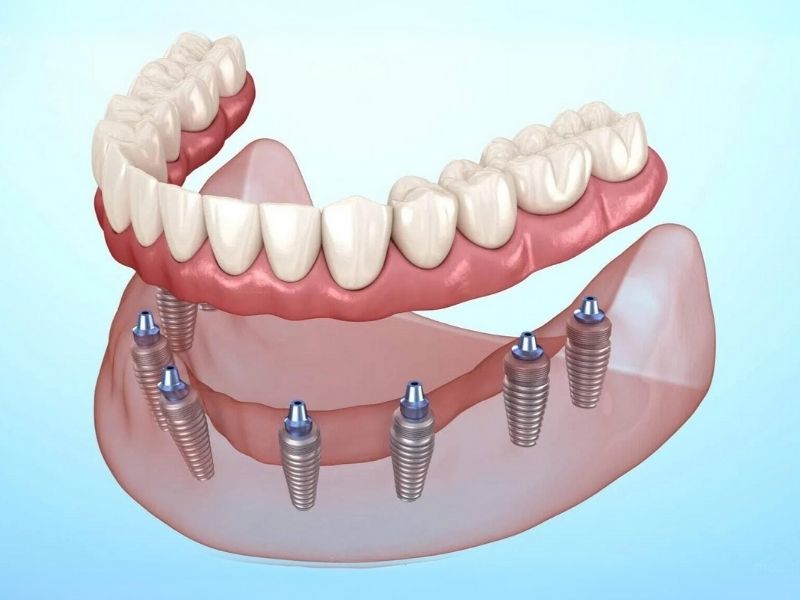

3. Full Mouth Implants

A fixed full-arch solution — ideal for patients who have lost most or all teeth.

Full Mouth Implants (All-on-4 / All-on-6)

A fixed full-arch solution — ideal for patients who have lost most or all teeth. -

Implant-Supported Dentures

Stable, comfortable, and secure dentures anchored on implants.